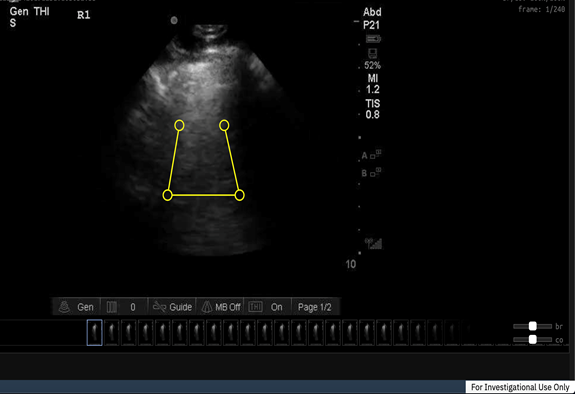

Medoは、シンガポールで設立され、カナダのエドモントンに本社を置くAIヘルスケアスタートアップです。AWS診断開発イニシアチブの支援を活用して、Medo Lungソリューションの開発を加速させました。Medo Lungは、肺の超音波スキャンを素早く行い、AIアルゴリズムで精査することで、患者の肺機能が正常であるか、COVID-19に関連する重篤な合併症の多くにつながる間質性肺炎などの合併症を患っていないかを検出できるようになります。このスキャンは、COVID-19検査を行うクリニックにおいて数千人の患者に実施することができ、緊急性の高い患者を特定することで、迅速かつ正確なトリアージを支援することができます。これにより、患者、特に高齢の患者が、どうしても必要な場合を除き、外出して医療機関に行く必要がなくなり、医療資源を効果的に利用しながら、潜在的な感染を避けることを支援します。

MedoはAWSと超音波を活用することで、放射線科医や臨床医による肺やその他の病状の診断を容易にすることができるようになりました。その結果、医療従事者は一般的な疾患と重篤な疾患をより迅速かつ正確に診断することができ、個々の患者に適した治療方針をより迅速に把握することができます。

Medoは現在、カナダでMedo Lungソリューションを試験的に導入しています。COVID-19に加えて、Medo Lungは、肺炎、胸水、気胸、肺水腫などの疾患にも対応しています。

Medo 共同創業者 のDavid Quail(デイビッド・クエイル)氏は、次のように述べています。「COVID-19により、最も必要とされる診療現場であらゆる医療従事者が実施でき、患者に快適かつ安全な環境を保つことができるAI診断の必要性が改めて認識されました。医用画像の利用を民主化し、できる限り多くの人々に当社のソリューションを提供するという当社のビジョンはさらに具体化しました。Amazon SageMakerやAmazon Textractなどの先進的なAWSのAI/MLサービスを利用することで、短期的にも、コロナ後を見据えた長期的にも、患者さんに大きな変化をもたらすMedo Lungを開発することができました」

放射線科医 兼Medo 共同設立者のJeevesh Kapur(ジーヴェシュ・カプール)博士は次のように述べています。「超音波による自己診断を世界各地で民主化するという私たちの取り組みを可能としているのは、人工知能と機械学習です。AWSを活かすことで、患者の診療や管理に必要なインフラがない場所も含めて、患者のアウトカムを大きく改善することができました。臓器をスキャンするのにかかる時間はわずか数秒で、我々のアルゴリズムは1分以内に信頼性の高い結果を提供し、医用画像へのアクセスと初期段階における信頼性の高い診断をすべての人に提供します」